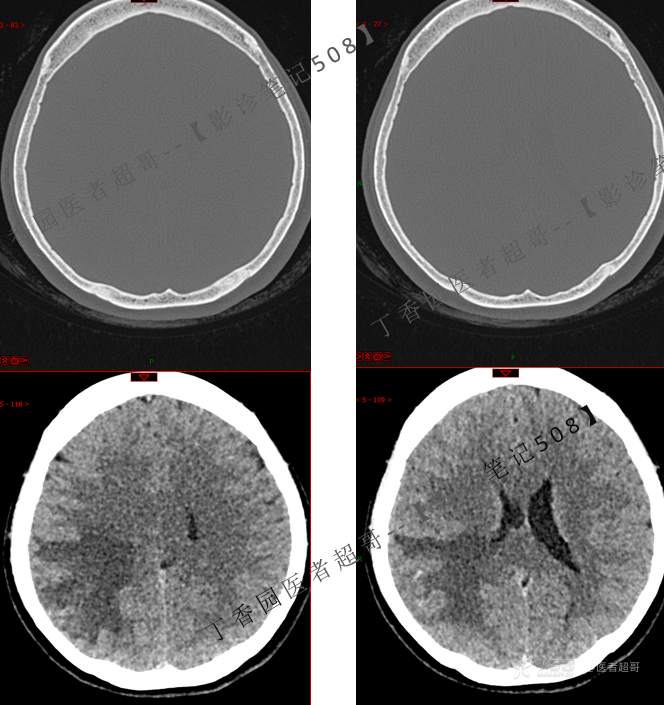

【影诊笔记508】同病异影,个人感觉有难度,欢迎分析,领丁当!有详细术程及病理!

主 诉:突发一过性意识不清伴肢体抽搐5天余。

现病史:患者5天余前无明显原因及诱因出现一过性意识不清,伴肢体抽搐,持续约2-3分钟,后意识逐渐恢复,无明显头痛头晕,无恶心呕吐,无肢体抽搐,无呼吸困难,无二便失禁,后就诊于当地医院,行颅脑CT示“颅内占位性病变”,予以药物对症治疗,具体不详,门诊以“颅内占位性病变”,收入我科。患者自发病以来,未进饮食,近期体重无明显变化。